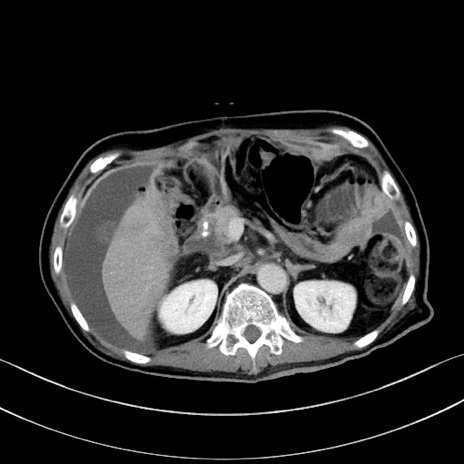

症例28(横断像)

【症例】60歳代男性

【現病歴】胃癌にて胃全摘後。食思不振が悪化し、夜中に嘔吐することがある。

【既往歴】胃癌、胃全摘、脾摘、胆摘後

【データ】WBC 5900、CRP 10.56